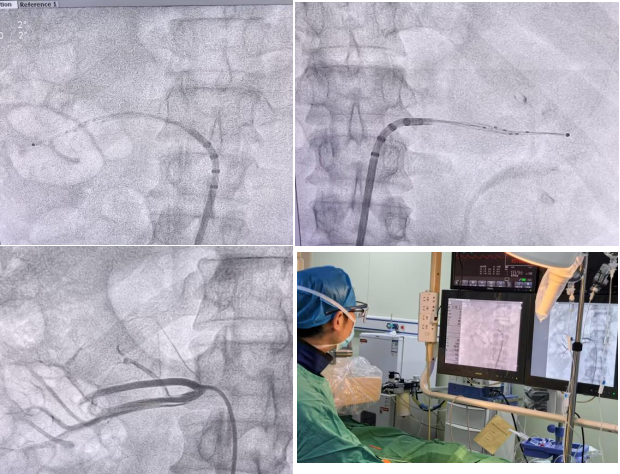

手术过程简洁顺畅,王正忠手术团队凭借精湛的医术和丰富的经验,通过股动脉穿刺将消融网篮精准送达肾动脉,对51个靶点完成了充分消融,整个手术耗时仅60分钟。术后观察到患者血压平稳下降至正常范围,消融后肾动脉无痉挛、无狭窄、无夹层等并发症。根据近一个月来的术后随访,患者血压一直保持在合理范围,手术获得圆满成功。

△王正忠团队RDN手术过程